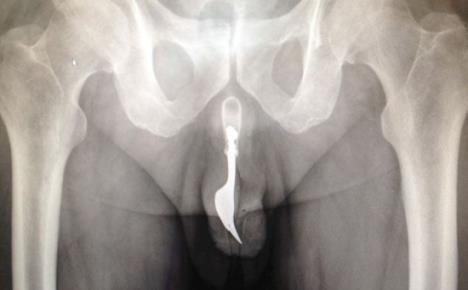

Dedi (70) se zaglavila viljuška u penisu tokom masturbacije!

Doktori su na više načina pokušavali da izvuku predmet iz čovekovog penisa, ali su na kraju to uradili "povuci - potegni" metodom, s puno lubrikanta

ASUTRALIJA - Starac koji ima čak 70 godina tokom seksa je povredio genitalije, a u bolnicu u Kanberi došao je žaleći se na krvarenje polnog organa.

Napokon, priznao je lekarima da je bizarna povreda nastala tako što je, uz pomoć viljuške, pokušao sebe da dovede do orgazma.

Uprkos nesnosnim bolovima koje je trpeo zbog metalnog predmeta koji mu se zaglavio u penisu, nesrećni perverznjak je 12 sati skupljao hrabrost da ode kod lekara. Doktori su na više načina pokušavali da izvuku predmet iz čovekovog penisa, ali su na kraju to uradili "povuci - potegni" metodom, s puno lubrikanta.